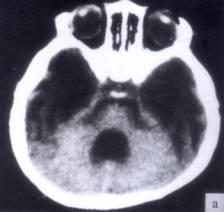

问题 病历摘要:??患者女性,10岁。结核性脑膜炎愈后8月,头痛伴恶心呕吐1周,并渐加重。体检:神清,精神差,反应迟钝,双眼底视神经乳头水肿,双眼外展差,余未见明显异常。 下列关于脑积水的叙述哪些是正确的?

选项 A.按阻塞部位分:梗阻性脑积水和交通性脑积水 B.按脑脊液蓄积部位分:内部性脑积水和外部性脑积水 C.正常颅压脑积水是指脑室扩大,但脑室内压力正常 D.正常颅压脑积水主要症状是步态不稳、记忆力障碍及尿失禁 E.儿童脑积水多为先天性和炎症性病变所致 F.成人脑积水多为颅内肿瘤、蛛网膜下腔出血和外伤所致 G.婴儿脑积水典型症状有Macewen征、日落征等